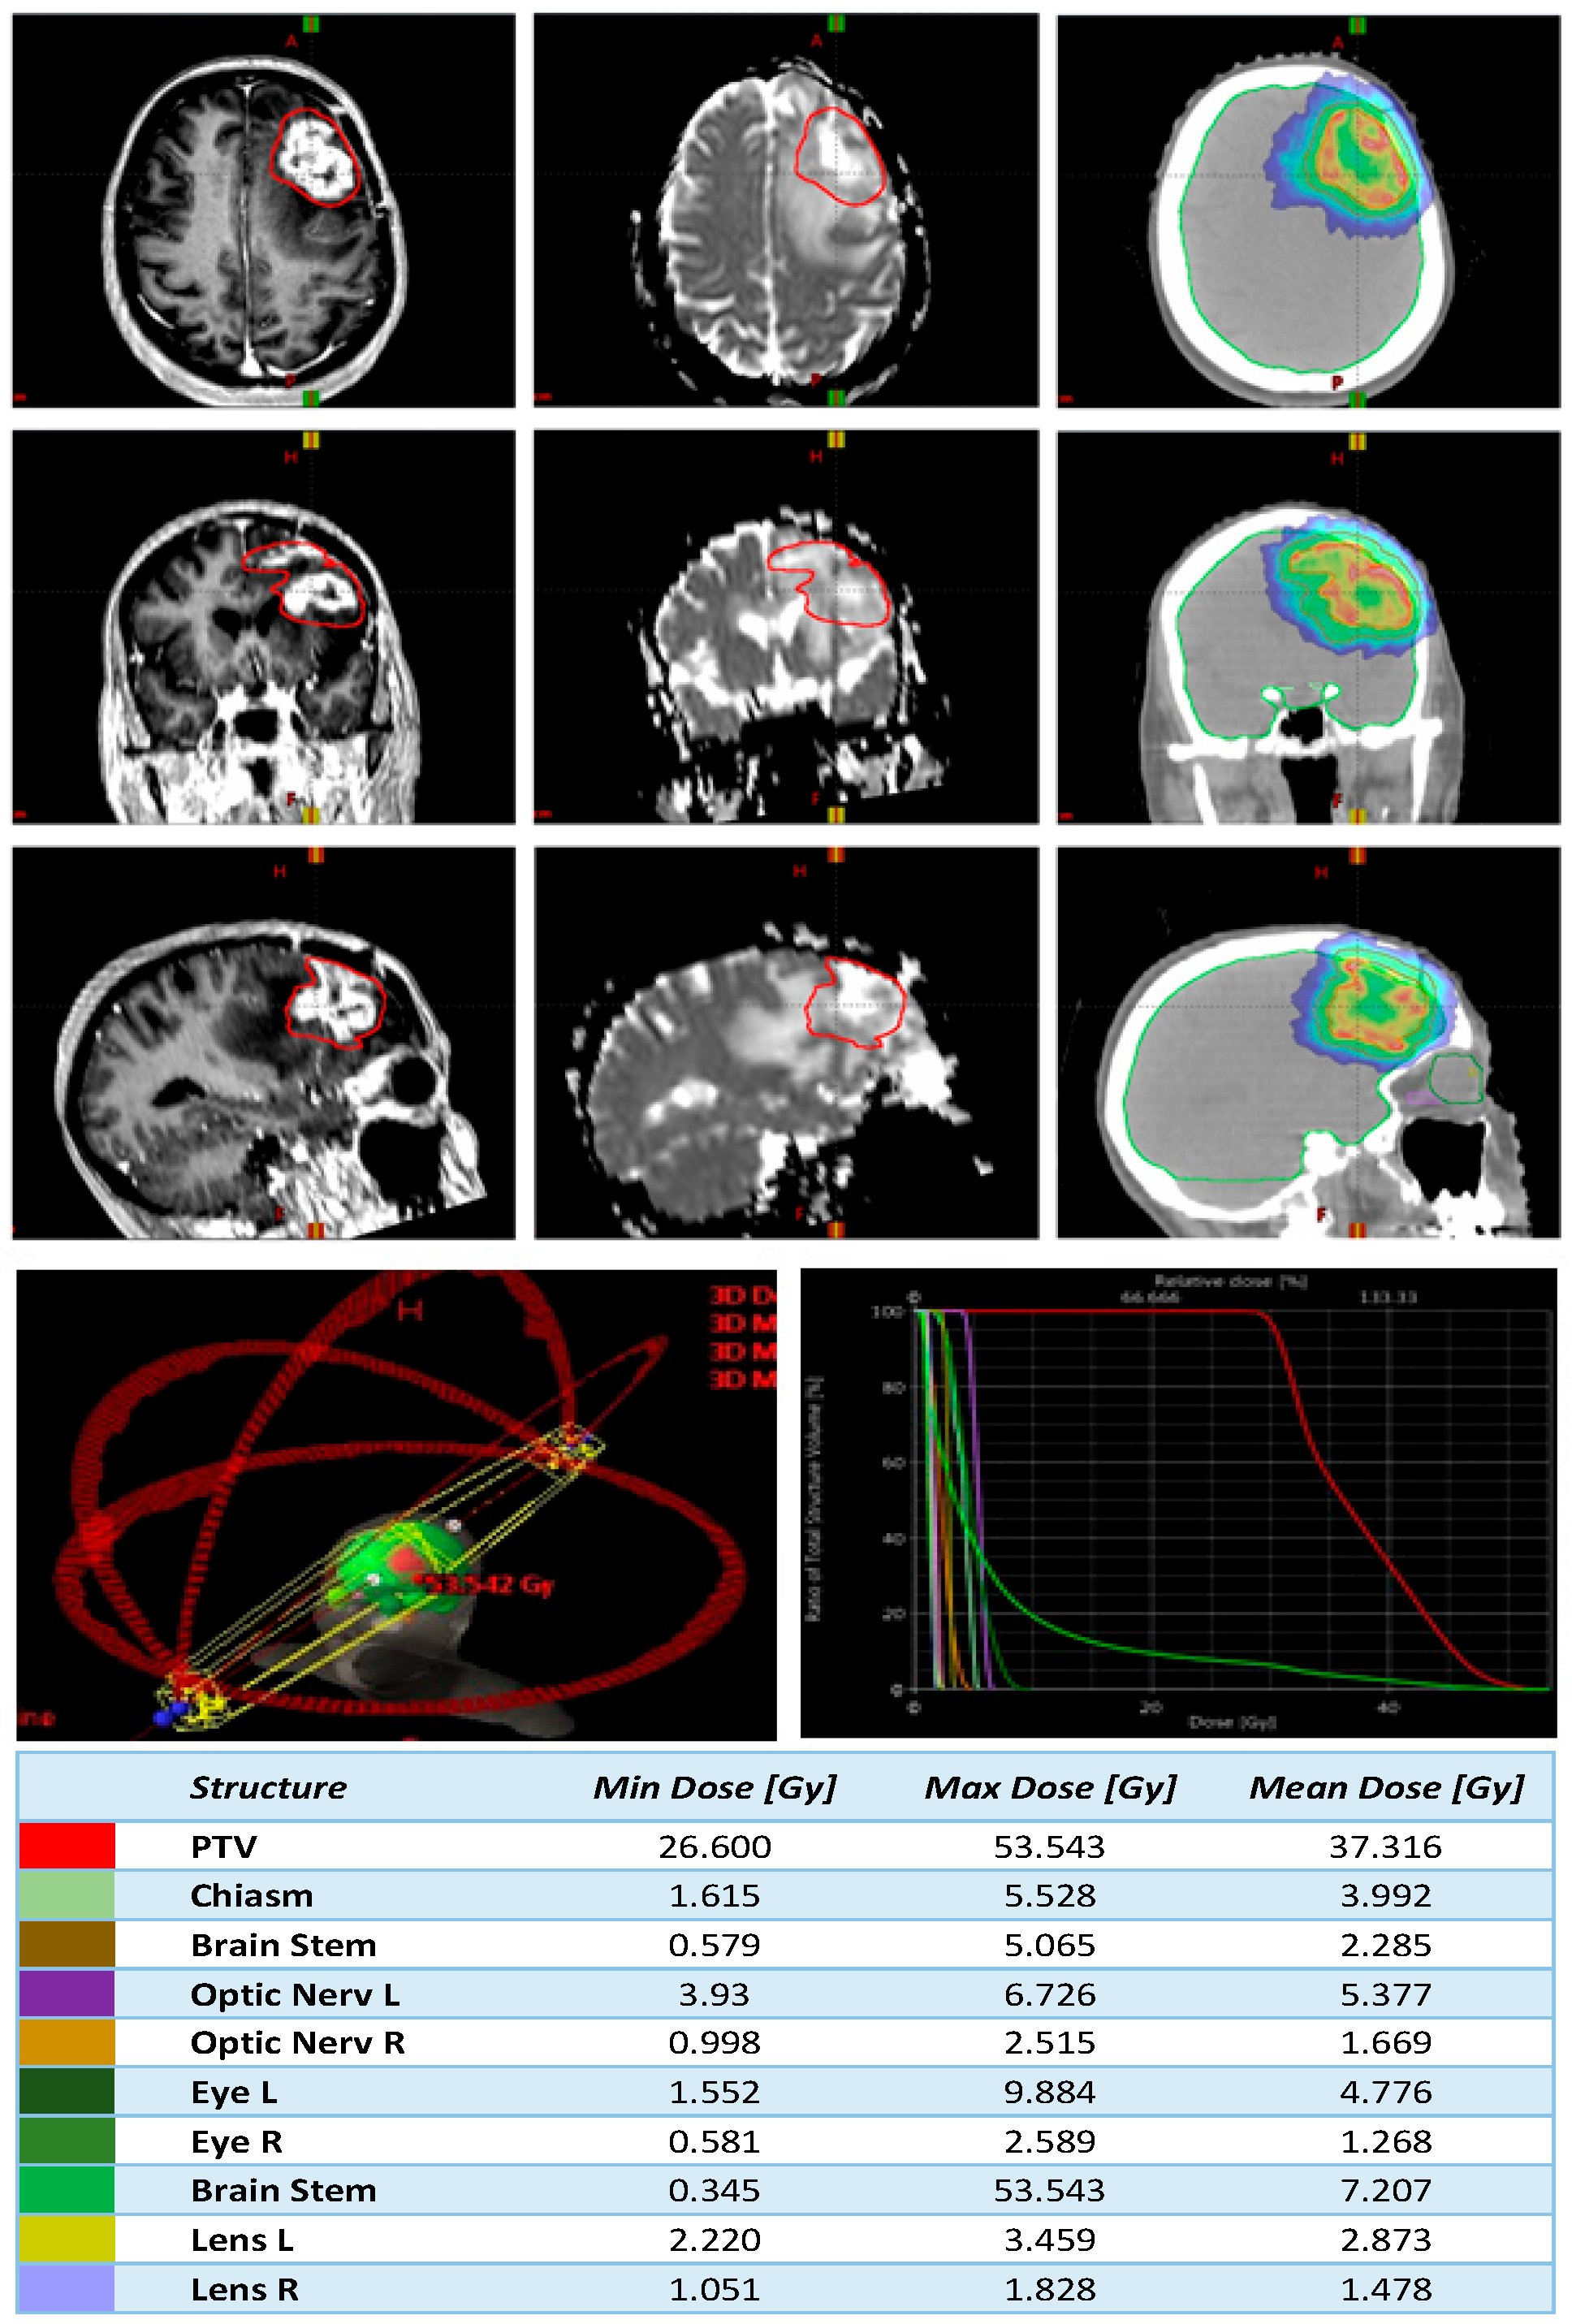

2.5. Planning

3.1. Treatment Characteristics